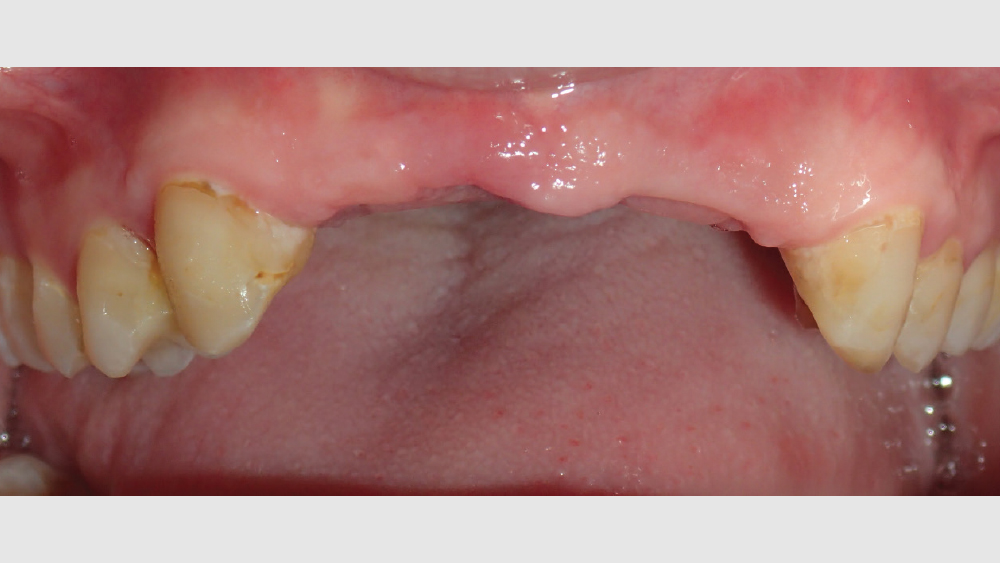

This patient came to me with four missing anterior teeth in positions #7–10. He had been missing these teeth for some time and was wearing a temporary denture to address the cosmetic issue this created. When he came to my practice, he was in a financial position to solve the problem permanently with implant restorations. Based upon the anterior space available and the fact that the patient’s surrounding tissue was in good health, I chose to move forward with Hahn™ Tapered Implants and BruxZir® Esthetic restorations.